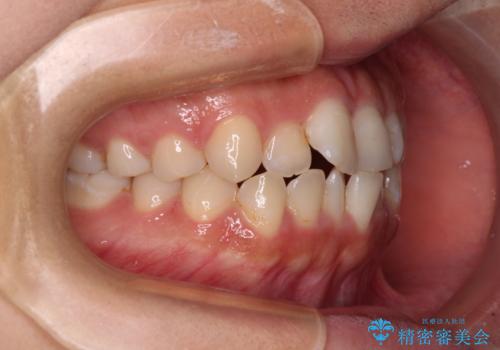

- 前歯のデコボコを気にして来院された患者様です。

マウスピース矯正のような自己管理の煩わしさがなく、早く治療を終えたいとのことで、ワイヤー装置による矯正治療を行うこととしました。

当初予定通り、1年で治療を終えることができました。